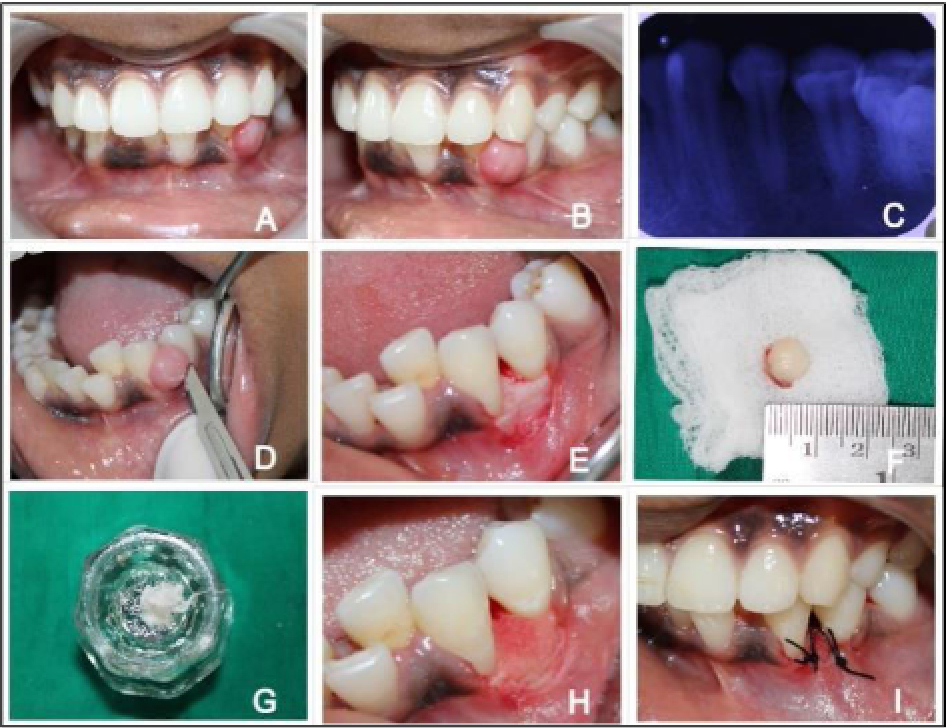

Management of Mucosal Fenestration and Palatogingival Groove (2015)

OSSEOGRAFT ® (DMBM - Xenograft)

&HEALIGUIDE ® (Bioresorbable GTR/GBR Membrane)

Treatment of peri-endo Lesion (2015)